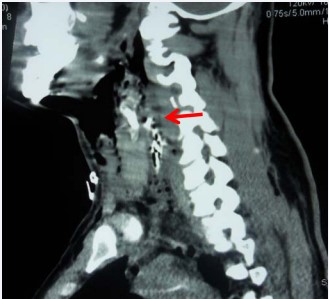

and CT scan neck with gastrographin swallow (Figure 3)

Figure 3: CT scan neck with gastrographin swallow Sagittal cut. Showing loss of cervical lordosis denoting neck muscles spasm, widening of the prevertebral space due to edema and surgical emphysema. Ba leak into the retropharyngeal space (arrow) is noted at the level of upper border of C4. were done. They were transferred to the operating theater; external neck examination was done to locate the missals’ inlets and exits.Direct laryngeal examination was done under general anesthesia (GA) followed by tracheostomy and neck exploration through a wide U-shaped neck incision. Strap muscles were cut exposing the larynx and pharynx that were skeletonized and separated from the carotid sheath on both sides. Vascular injuries were managed when present by vascular surgeons. During neck exploration the assistant harvested the AFLG as follows; the thigh is flexed to a level that allows knee flexion of 90° while being supported from below with packed drapes. The leg is fixed to the table at 150° adduction of the hip joint. An “S”-shaped incision line is marked 6 cm proximal to the lateral femoral condyle. This incision enables the harvest of a 10 X 20 cm fascial sheath. A transverse incision is made through the fascia distally while two-tissue forceps are used to hold and fasten the fascia. The fascial sheath is cut longitudinally with slightly opened tips of scissors. Skin is closed in layers using subcutaneous interrupted 4/0 Vicryl sutures and skin staples. The Free non-vascularized AFLG is fashioned and tightly sutured using 3/0 vicryl suture to the posterior pharyngeal wall covering the whole pharyngeal tear and in mid line to avoid collection beneath the graft (Figure 4).